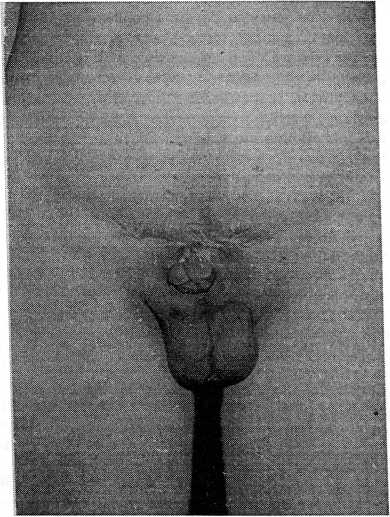

Половой член укорочен, подтянут к рубцу. В верхней части головка расщеплена, уретра отсутствует. Яички нормальных размеров, наружные гениталии имеют удовлетворительно развитый волосяной покров (рис. 2). Простата гипоплазирована, едва пальпируется.

Рис. 2.